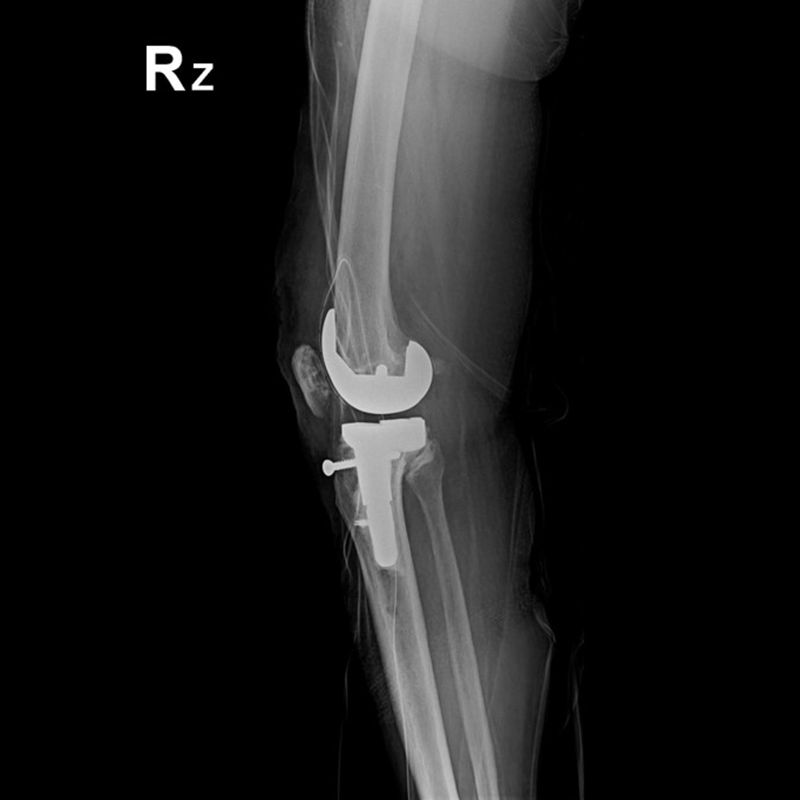

外院失敗本院再置換 首頁 案例分享 膝關節手術 外院失敗本院再置換 蕭女士 69歲 術前 術後 81歲 林女士 術前 術後 蕭女士 69歲 術前 術後 鄒女士 69歲 術前 術後 李女士 74歲 術前 術後 吳女士 71歲 術前 術後 謝女士 65歲 術前 術後